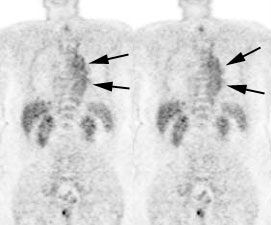

Prominent tracer uptake has also been described within the

Other areas in which brown fat uptake can less commonly be seen

Brown Fat: Prominent, symmetric supraclavicular tracer uptake was seen in this patient without a corresponding CT finding. Uptake in this area has been felt to be related to the presence of "brown" fat. |